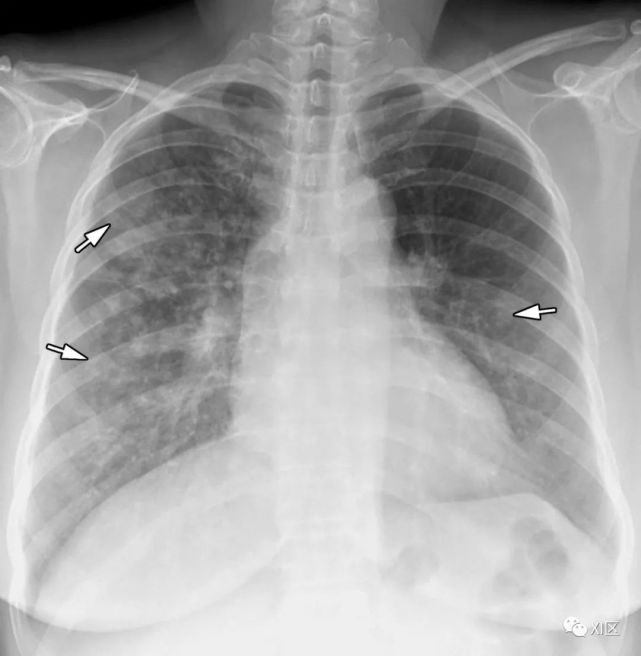

图8 20岁男子因腺病毒感染引起肺炎,伴有发热、咳嗽和呼吸困难。

(上) 最初的胸片显示左中下肺和右下肺区有不明确的斑片状实变和GGO(箭头)。同一天在叶间支气管水平(中)和肺下静脉水平(下)上获得的轴位胸部CT图像(厚度为5mm)显示不明确的斑片状GGO(箭头)和大叶实变(箭)。

Koo H J , Lim S , Choe J , et al. Radiographic and CT Features of Viral Pneumonia[J]. Radiographics, 2018, 38(3):719-739.